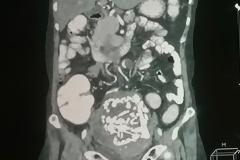

ΑΠΙΣΤΕΥΤΟ: Δείτε τι είχε στην κοιλιά της μία 60χρονη γυναίκα 36 χρόνια...[photo]

2

16:30:30

Κυριολεκτικά άναυδοι έμειναν οι γιατροί όταν ανακάλυψαν τι ακριβώς συνέβαινε στην κοιλιά μίας 60χρονης γυναίκας